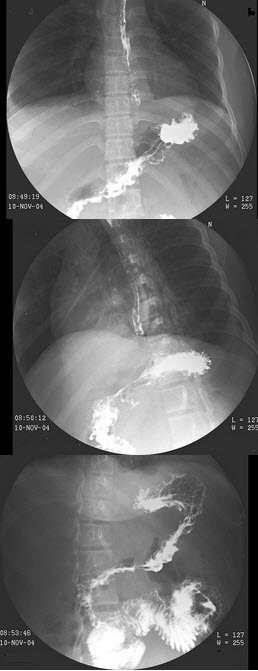

35、单项选择题

女,61岁,腹痛腹胀2年,结合图像,最可能的诊断为()

A.正常肠圈

B.十二指肠炎

C.降段憩室

D.水平段憩室

E.占位